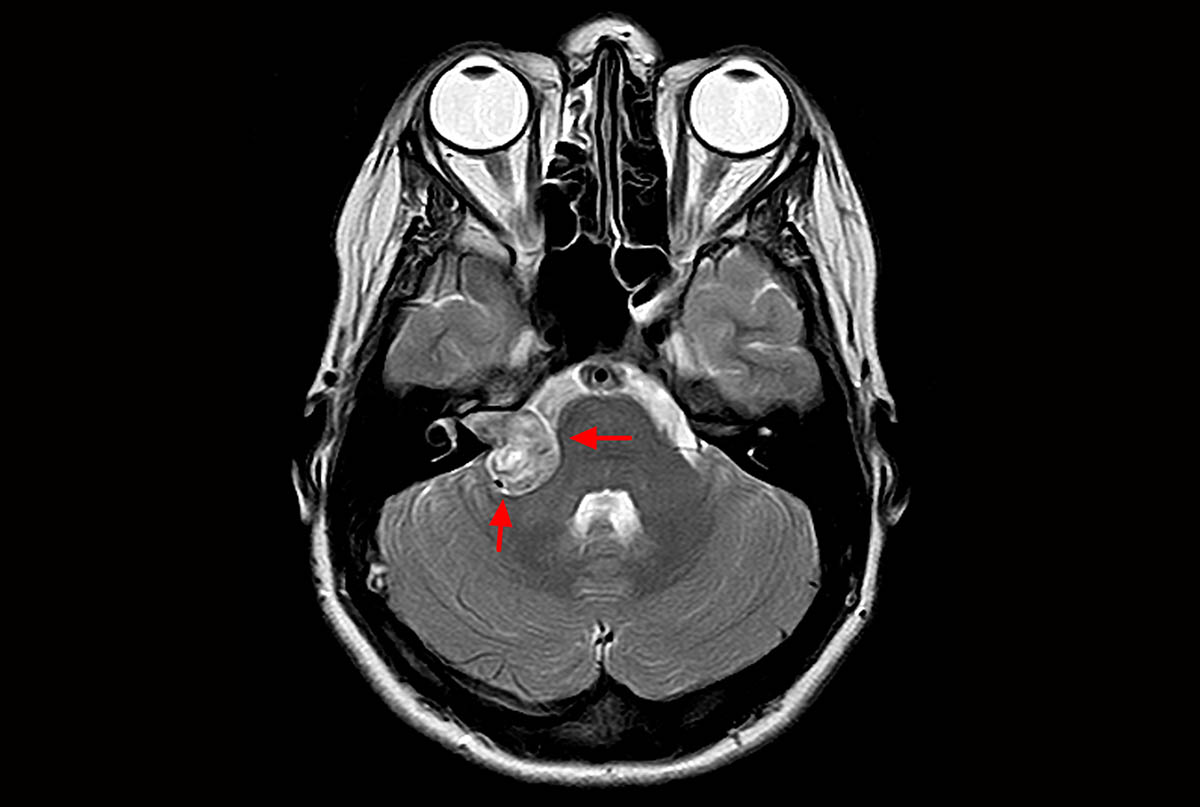

2. Инструментальная диагностика. Для подтверждения диагноза и детального изучения строения черепа используются методы визуализации. «Золотым стандартом» в диагностике краниосиностоза является компьютерная томография (КТ) с 3D-реконструкцией костей черепа. Это исследование позволяет с высокой точностью увидеть, какие именно швы закрыты, оценить степень деформации и спланировать хирургическое вмешательство. В некоторых случаях, особенно у детей первых месяцев жизни, может быть информативно ультразвуковое исследование (УЗИ) черепных швов. Магнитно-резонансная томография (МРТ) назначается реже, в основном для оценки состояния головного мозга, если есть подозрения на сопутствующие аномалии.

Мальформация Киари: обретение контроля над симптомами и будущим

Пациенты с мальформацией Киари часто сталкиваются с неопределенностью и тревогой из-за сложных симптомов. Наша статья предоставляет исчерпывающую информацию о заболевании, современных методах диагностики и лечения, помогая вам принять взвешенное решение.

Невринома слухового нерва: полный путь от симптомов до полного выздоровления

Столкнулись с диагнозом невринома слухового нерва и ищете надежную информацию? Наша статья подробно описывает все аспекты: от первых признаков, таких как шум в ухе, до современных методов нейрохирургического лечения и реабилитации.